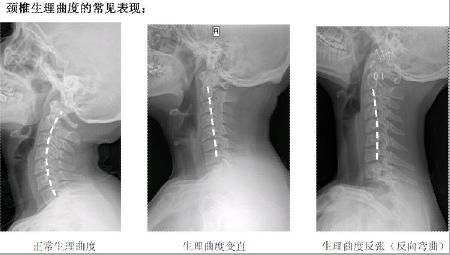

正常頸椎生理彎曲,可以使人呼吸通暢

從上面一組圖我們可以看出,頸椎正常的生理彎曲很重要。但現(xiàn)在,由于電腦的使用,很多人的頸椎都出現(xiàn)了不應(yīng)有的病變,頸曲度消失,甚至反張,會(huì)導(dǎo)致腦血出現(xiàn)障礙,引起包括頭暈、肩頸痛、手臂麻,以及頸心綜合癥等一系列問題,而昆叔正是由客戶的頸紋判定她的頸椎不好的。